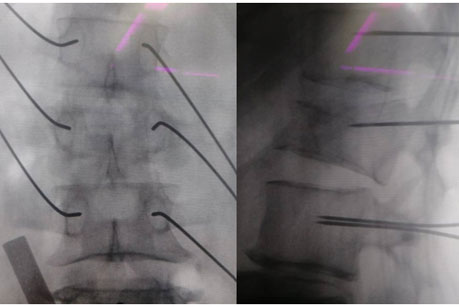

(在天玑骨科机器人辅助下准确置入克氏针)

通过精密的术前规划和术中机器人的精准定位,医生能够非常准确地在机器人引导下置入椎弓根螺钉。相比常规手术,机器人辅助下的脊柱手术切口更加微创,每个切口仅1厘米左右,却并不影响6枚椎弓根螺钉依次准确进入钉道,手术安全,出血少,术后即可以快速进行康复训练。